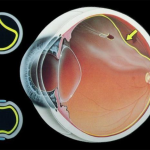

NHẬN BIẾT CÁC BỆNH LÝ VÕNG MẠC NGUY HIỂM

SKĐS - Võng mạc là lớp trong cùng của nhãn cầu tiếp nhận ánh sáng, truyền tín hiệu đến não thông qua hệ thống...